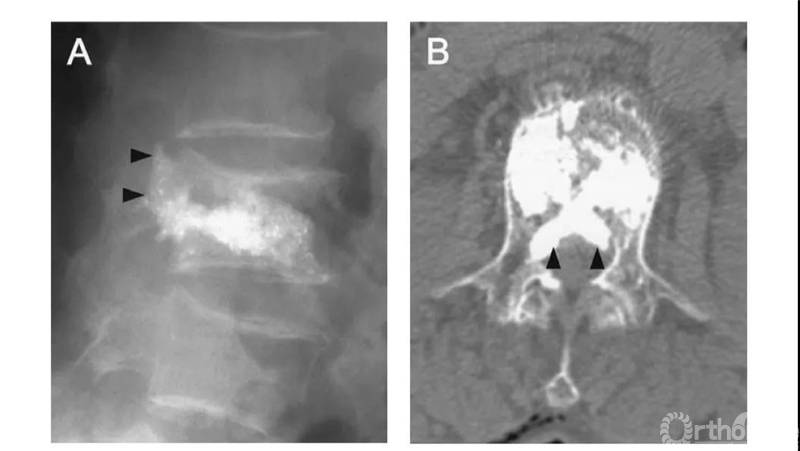

侧位X片看骨水泥在椎体里,CT显示渗漏进入椎管。